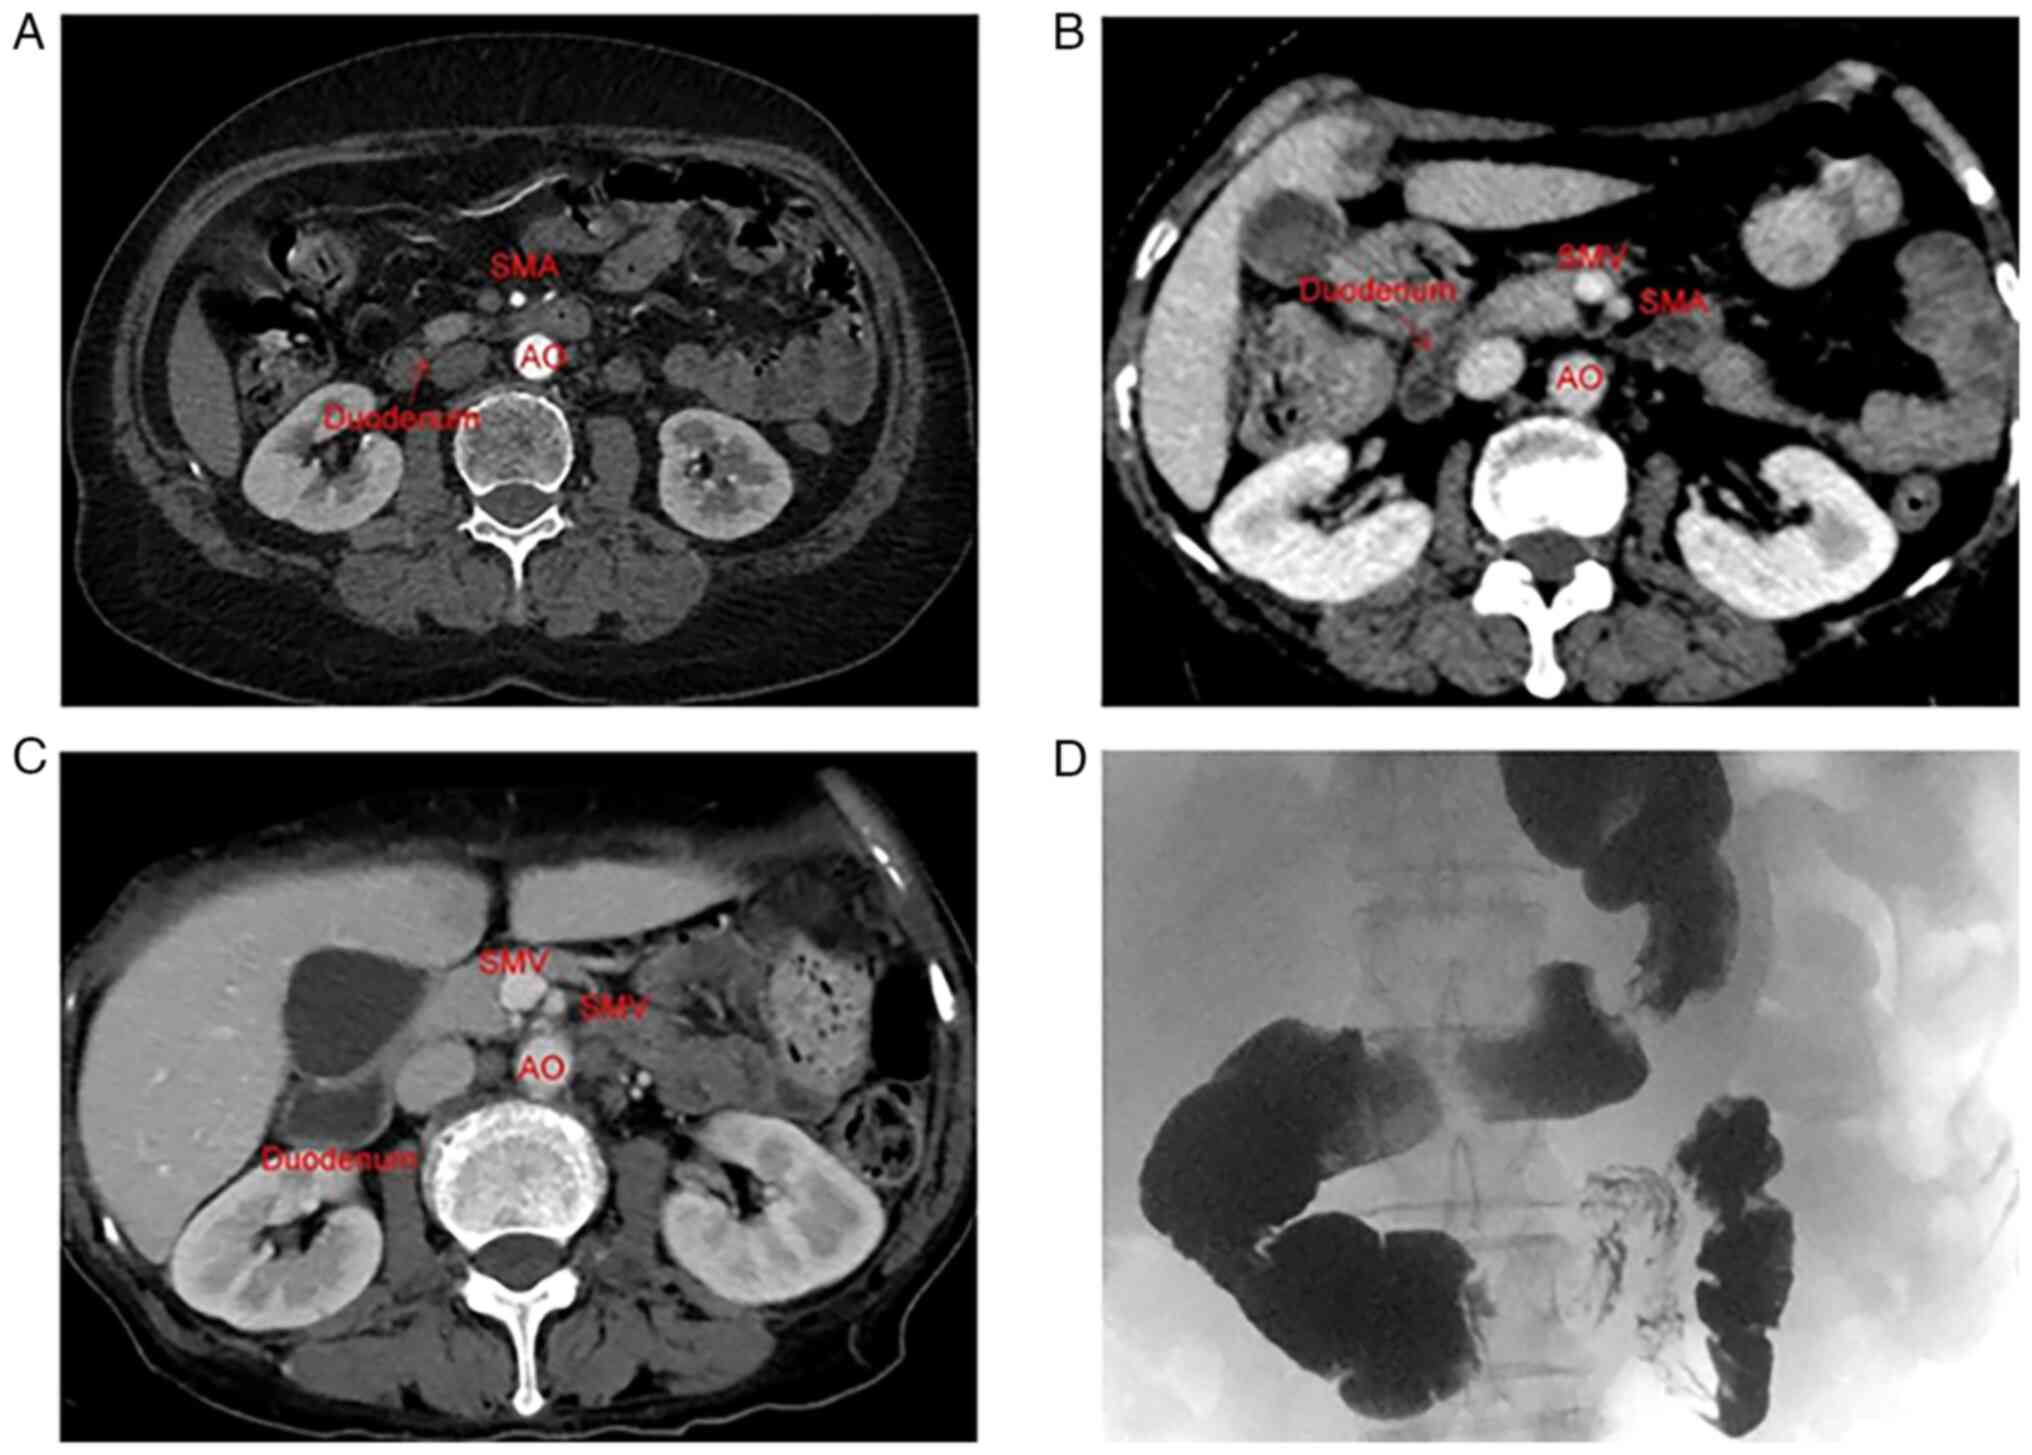

Superior mesenteric artery syndrome following esophageal cancer surgery: A report of two cases and a literature review

The present study describes two cases of superior mesenteric artery syndrome (SMAS) which occurred following esophageal cancer surgery. The first case was that of a 68‑year‑old woman who underwent left sided trans‑thoracic esophagectomy for esophageal squamous cell carcinoma. Specific symptoms, including bloating and postprandial vomiting, firstly appeared repeatedly 1 week following surgery. She was diagnosed with SMAS using a barium swallow (upper gastrointestinal series), and the symptoms did not improve following nutritional support treatment. Finally, the symptoms were relieved following a duodenojejunostomy. The second case involved a 66‑year‑old woman who underwent radical esophageal cancer resection. At 4 years after the surgery, the patient developed abdominal distension and postprandial vomiting. She was diagnosed with SMAS, again using an upper gastrointestinal series. Her symptoms were relieved following parenteral nutrition support. SMAS is a rare disease characterized by abdominal distension and vomiting. It is similar to the gastrointestinal manifestations caused by anastomotic stenosis and gastrointestinal reconstruction following esophageal cancer surgery, and it may also prompt thoracic surgeons to ignore the diagnosis of SMAS. Therefore, the possibility of SMAS occurrence in patients who have undergone radical esophageal cancer surgery, should be taken into consideration if they experience gastrointestinal symptoms, including abdominal distension and vomiting, following a rapid weight loss.

Figure 1

Figure 2

Figure 3